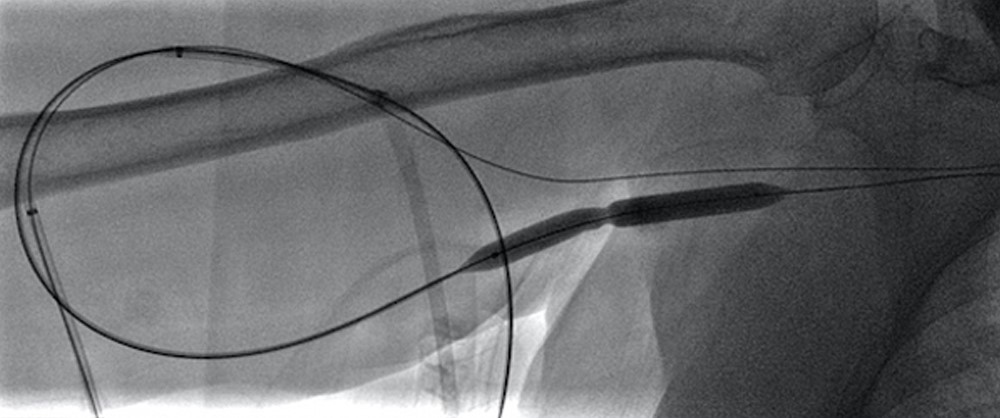

The VIABAHN® Device has proven success when treating thrombosed grafts1

Proven patency

- Exceeded KDOQI minimum guidelines for 3-month circuit primary patency for thrombotic patients (48%) whereas percutaneous transluminal angioplasty (PTA) did not (39%).1,2

- Increased primary patency in thrombosed grafts of both the target lesion and the circuit by ~50% when compared to PTA at 6 months.1

Fewer reinterventions

- Lowered the mean number of interventions over 2 years by 40% in thrombosed grafts.3